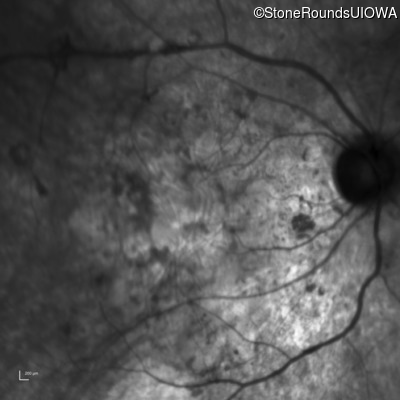

Infrared Fundus Photograph - Right - Hand Motion sc

Exemplar